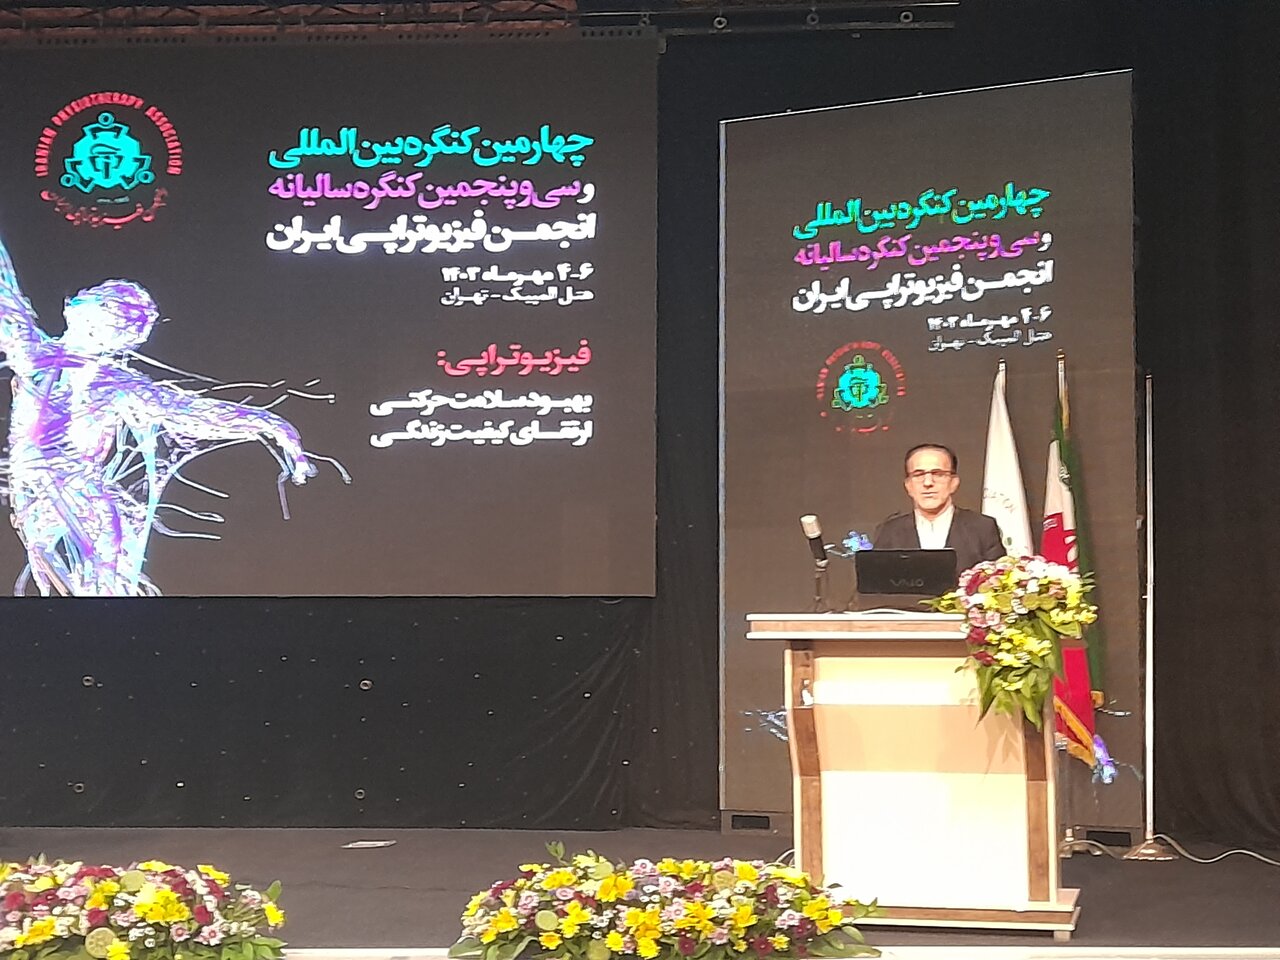

چهارمین کنگره بین المللی و سی و پنجمین کنگره سالیانه انجمن فیزیوتراپی ایران، از صبح چهارشنبه چهارم مهر 1403 در مرکز همایش های هتل المپیک تهران آغاز به کار کرد. - چهارمین کنگره بین المللی ...

51 - سلامت فصل عمده ای از دوران پیری بر دوش فیزیوتراپیست ها است

مهر- ورزشی- 6 ماه پیش - چهارشنبه 4 مهر 1403، 09:30 74333054

مهر- ورزشی- 6 ماه پیش - چهارشنبه 4 مهر 1403، 09:30 74333054

چهارمین کنگره بین المللی و سی و پنجمین کنگره سالیانه انجمن فیزیوتراپی ایران، از صبح چهارشنبه چهارم مهر 1403 در مرکز همایش های هتل المپیک تهران آغاز به کار کرد. - چهارمین کنگره بین المللی ...